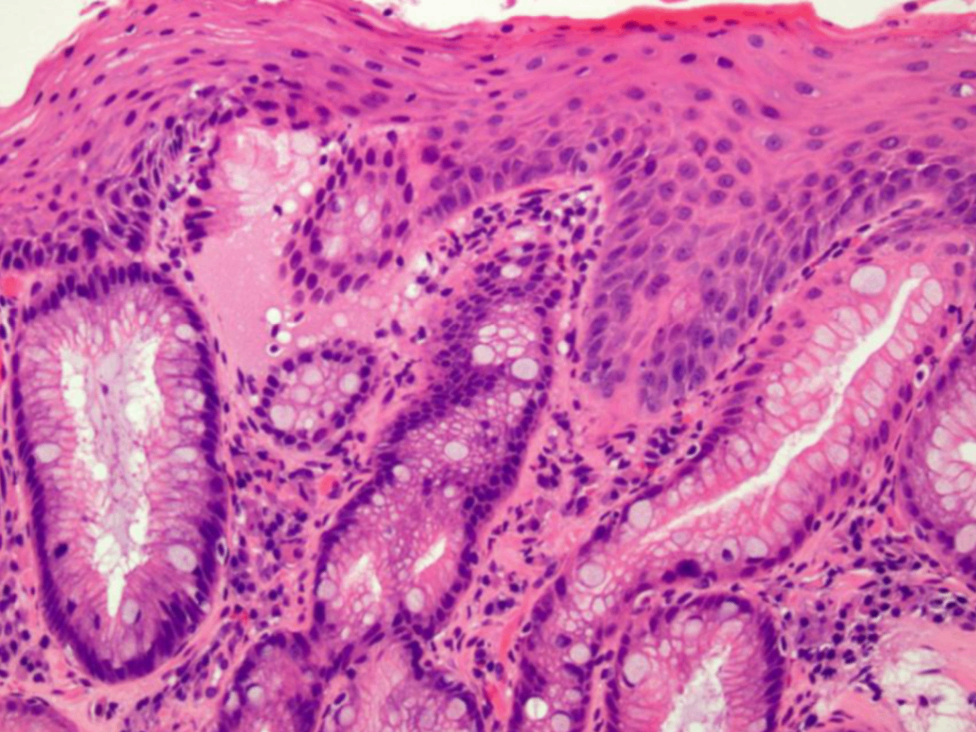

• 해당 환자에서는 지속된 위식도 역류로 인한 Barrett’s esophagus가 관찰된다. Barrett’s esophagus는 지속된 위식도 역류로 인해 esophagogastric junction에서 편평상피세포가 원주상피세포로 화생하며 생긴다.

• Barrett’s esophagus의 가장 중요한 합병증은 바로 식도선암 (esophageal adenocarcinoma)이다.

병리 소견 | 점액 분비 세포로 구성, 샘 구조(glandular pattern) | 편평상피 세포 증식과 keratin pearls & intercellular bridges |